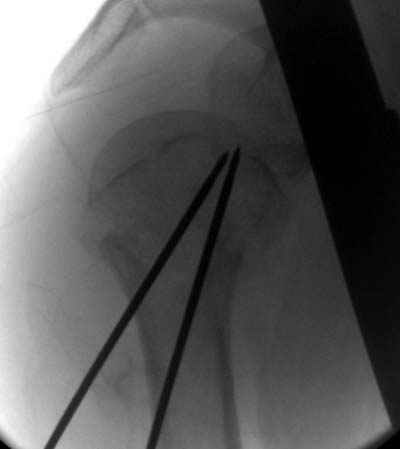

Да. У нас довольно скромный опыт такого остеосинтеза (по 2 случая - плечо и наружная лодыжка), дошли до использования самого простецкого троакара, через который мы сверлим кость и вводим 6 мм стержни, когда накладываем аппарат. Соответственно, в качестве забойника отлично работает любой стержень от аппарата Илизарова. Еще из наших туземных особенностей - страшная любовь к спицевым дистракторам, поэтому делали в нем. Результат у этой дамы неизвестен, т.к. она из области и уехала рожать сразу после остеосинтеза, сейчас прошло больше 5 месяцев...

Что-то, наверно, сделали мы не совсем оптимально, поскольку у Анатолия Федровича и его соратников как-то красивее "раскрываются" спицы в головке плеча - надеюсь, он прокомментирует и подскажет, что надо подправить.